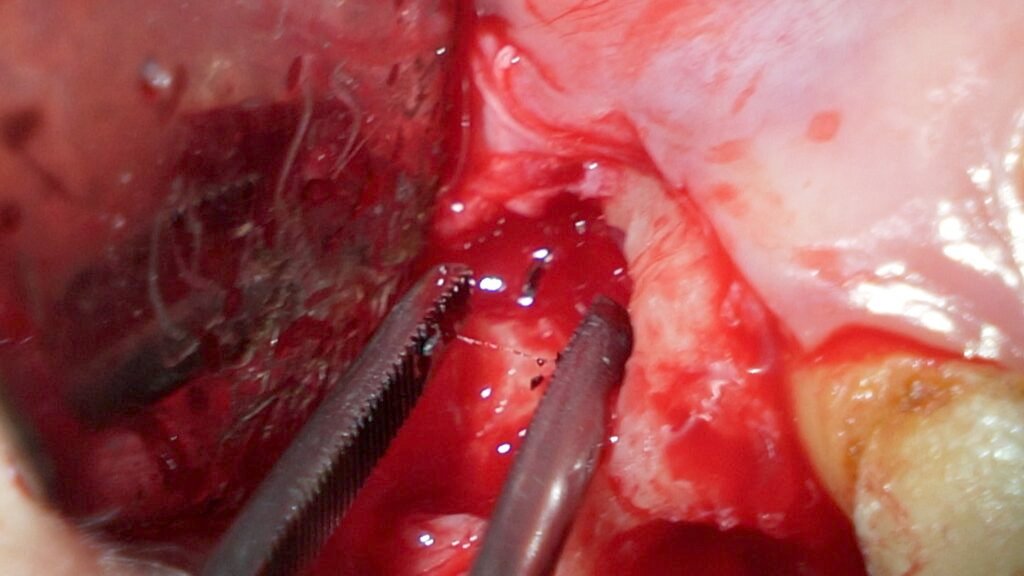

I then extracted the tooth, which showed overfilled canals, but unfortunately, the broken file did not come out with the tooth. A follow-up X-ray confirmed the file remained in the bone. Using a high-magnification microscope and special illumination, I performed a surgical procedure to carefully remove the broken file from the bone. The patient’s discomfort was resolved after a few days, and she recovered well.